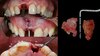

Cas d’extraction implantation immédiate avec perte totale de la paroie osseuse vestibulaire : Gestion en un seul temps (Implant + chirurgie osseuse + chirurgie gingivale).

Technique mise au point par le Dr Da Rosa nommée IDR (Immédiate Dentoalvéolar Restauration), le bloc cortico-spongieux est prélevé sur le secteur postérieur de la tubérosité maxillaire et designé pour une insertion « verrouillante ». Le gap de 2mm entre l’implant et le bloc greffé est comblé à l’aide d’os spongieux 100% autogène prélevé sur le même site. Pour optimiser les tissus mous un greffon conjonctif tubérositaire est également positionné en « poncho » autour de la couronne provisoire permettant une sur-correction.

4mois de cicatrisation sont nécessaire depuis le jour de l’intervention pour la couronne d’usage.